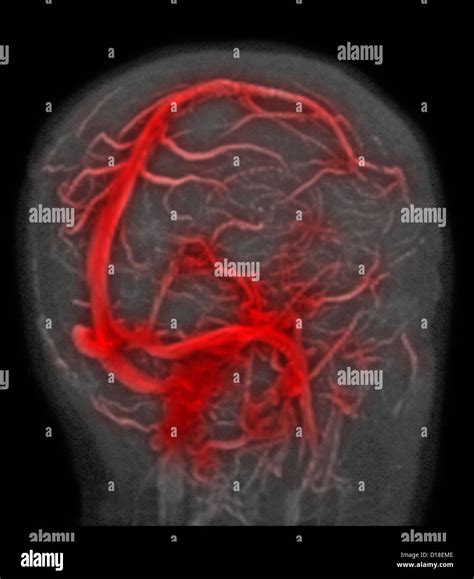

Magnetic Resonance Venography (MRV) is a sophisticated medical imaging technique that uses magnetic fields and radio waves to generate detailed images of the cerebral veins. Unlike a standard MRI, which primarily looks at the brain tissue itself, an MRV is specifically designed to assess blood flow and identify potential abnormalities within the venous system.

Doctors frequently use this scan to detect issues such as cerebral venous thrombosis (blood clots in the brain's veins), narrowing of the veins (stenosis), or other vascular anomalies that might be affecting cerebral circulation.